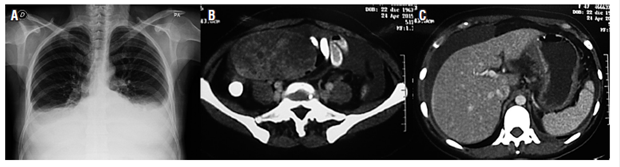

Computerized axial tomography (CT) with contrast of the abdomen on April 24, 2015 showed a slight increase in the number of retroperitoneal nodes. The uterus was enlarged with the presence of myomas and a well-defined solid heterogeneous right adnexal mass with smooth contours that measured 110 x 79 x 71 mm. There was a moderate amount of free liquid in the cavity, the gastric wall of the corpus was thickened, and the peritoneum was nodular (Figure 1).

Figure 1 A. Chest x-ray showing plural effusion. B. CT scan showing right adnexal mass. C. CT scan showing peritoneal fluid and thickening of stomach walls.